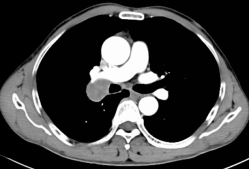

57岁的王先生因咳嗽、咯痰在外院行胸部CT检查提示:右肺上叶支气管开口区占位性病变,伴腋窝淋巴结肿大。患者反复辗转多家医院,院外共行5次活检均未确诊。

CT提示病灶在右肺上叶支气管开口区,腔外为主)

随后,患者又到上级医院行PET-CT提示:“右肺门占位伴右肺上叶支气管阻塞,腋窝淋巴结肿大,考虑肿瘤伴转移可能。”